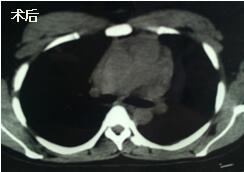

當(dāng)看到病人的CT等外院各項(xiàng)檢查時(shí),我頭皮發(fā)麻,心頭發(fā)怵:巨大的腫塊占據(jù)著整個(gè)縱隔,壓迫心臟,與血管關(guān)系密切,初步考慮侵襲性胸腺瘤、胸腺癌或淋巴瘤等,合并腎功能不全,無(wú)法完整切除,手術(shù)風(fēng)險(xiǎn)大,手術(shù)并不能提高病人長(zhǎng)期生存率,換言之,小伙子等待的是生命的立即終結(jié)。

當(dāng)看到病人癥狀緩解,復(fù)查胸部CT幾近完美,我們那種自豪感油然而生。偶爾去治愈,常常去幫助,總是去安慰,我們深知,小伙子的人生之路并不長(zhǎng),只能深深祈禱他在我們的治療下能走得更遠(yuǎn)一些,能把剩下的日子走的更充實(shí)一些。而我們?cè)谀軌驇椭说臅r(shí)候,別一味地去安慰,永不言棄,是我們這一群胸外人堅(jiān)貞的信念。